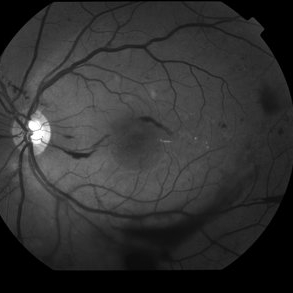

Proliferative Diabetic Retinopathy with Vitreous Hemorrhage - Red Free

Oct 18 2012 by Suber S. Huang, MD, MBA, FASRS

30 year old diabetic man with proliferative diabetic retinopathy and vitreous hemorrhage

Photographer: Stacie Hrvatin

Condition/keywords: cotton wool spots, neovascularization (NV), subhyaloid hemorrhage, vitreous hemorrhage